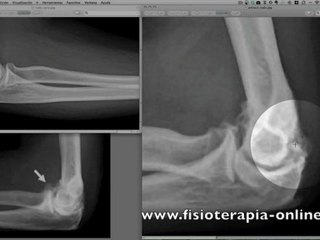

Condromalacia rotuliana. Signos radiológicos.

Visita - Todo sobre fisioterapia.br Muestro los signos radiologicos mas comunes en las radiografias de la rodilla en el caso de la condromalacia rotuliana.br Es la parte mas importante en el diagnostico de la condromalacia rotuliana.